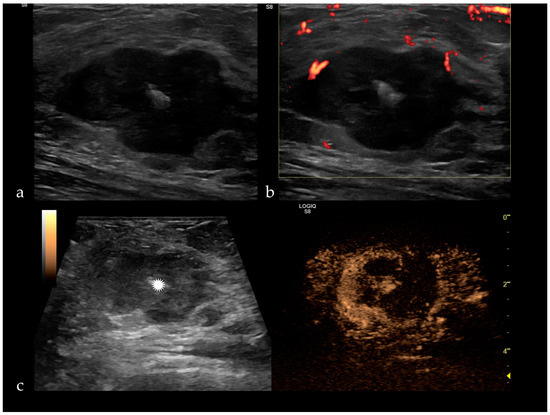

Figure 3. (a) Triple negative breast cancer appears as a hypoechoic, irregular mass, with a central hyperechogenity represented by a clip (white star), peripheral vascularization on Doppler ultrasound (b), inhomogeneous enhancement and filling defects after SonoVue administration (c).

6. Diagnosis Limitations of CEUS

CEUS, like any imaging technique, has its limitations. It has a low diagnostic performance in detecting DCIS, early-stage invasive ductal carcinoma (IDC) and also regarding rare and unusual types of breast cancer. For instance, triple-negative cancers in CEUS have a regular shape, sharp margins, the same size as in gray-scale ultrasound, present hypo or iso-enhancement with a slow wash-in and no penetrating vessels or crab-claw pattern (Figure 3). Mucinous carcinomas have the same size or are smaller compared with gray-scale ultrasound. They can present either a slow wash-in with hypo-enhancement due to the lack of vascularization and rich mucus content or can have a fast wash-in, with intense and heterogeneous uptake of the contrast agent [8]. Medullary carcinomas have a regular shape, well-defined margins, homogenous enhancement and no change in size before and after contrast enhancement, but they can present penetrating or tortuous surrounding vessels [42].